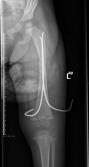

儿童陈旧性孟氏骨折

术前前臂侧位片

儿童陈旧性孟氏骨折,术前桡骨小头陈旧性脱位,经截骨矫形治疗后1个月,桡骨小头已复位,患儿肘关节屈伸功能(1-2图),前臂旋转功能(3-4图)正常